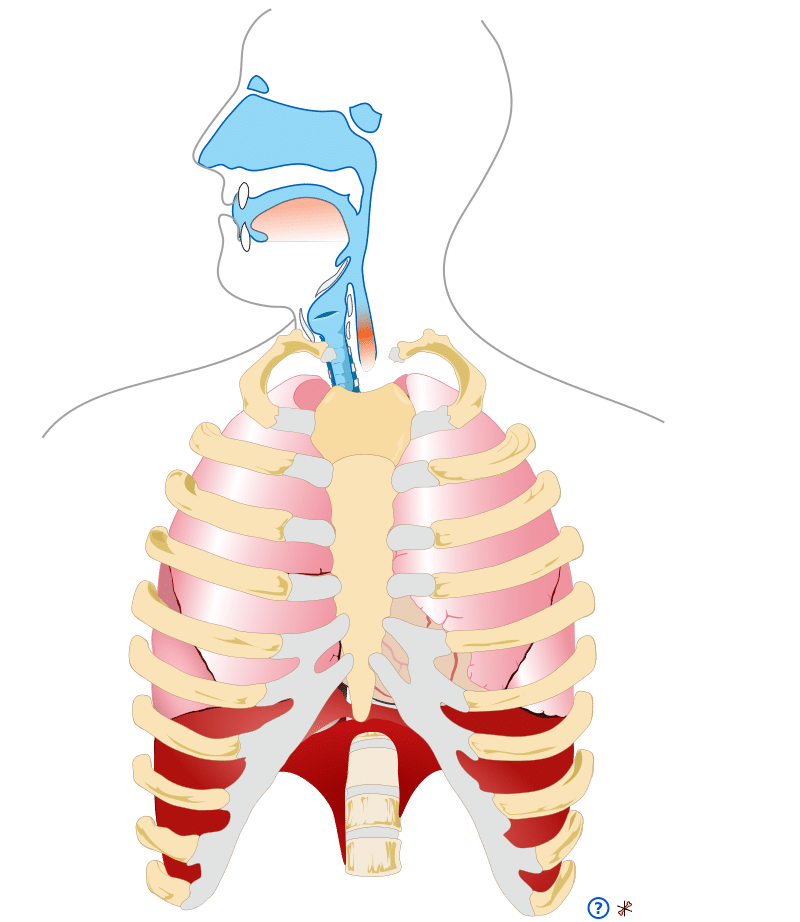

Upper Respiratory System

The upper respiratory system involves the nose, mouth, oropharynx, trachea, and upper airways

The upper respiratory system involves the nose, mouth, oropharynx, trachea, and upper airways